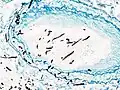

On microscopy, Aspergillus species are reliably demonstrated by silver stains, e.g., Gridley stain or Gomori methenamine-silver.[27] These give the fungal walls a gray-black colour. The hyphae of Aspergillus species range in diameter from 2.5 to 4.5 μm. They have septate hyphae,[28] but these are not always apparent, and in such cases they may be mistaken for Zygomycota.[27] Aspergillus hyphae tend to have dichotomous branching that is progressive and primarily at acute angles of around 45°.[27]